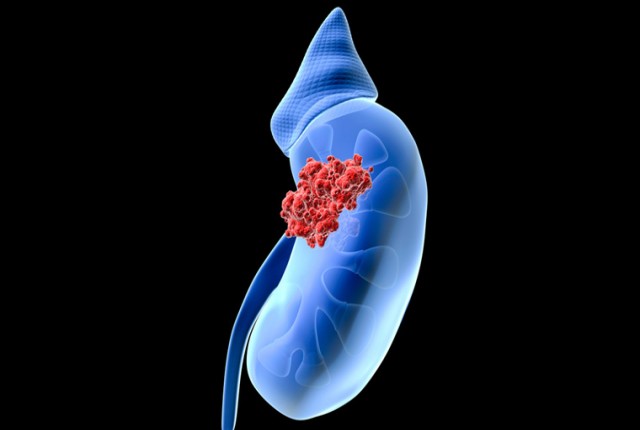

Ο καρκίνος του νεφρού παρουσιάζεται συνήθως μετά τα 50 έτη και ειδικά στους άντρες, η συχνότητα είναι διπλάσια από ό,τι στις γυναίκες. Δυστυχώς, δεν έχει ιδιαίτερα συμπτώματα στα αρχικά στάδια, γεγονός που καθιστά τη διάγνωσή του δύσκολη.

Στα αρχικά στάδια, δυστυχώς, σπάνια υπάρχουν συμπτώματα, και αυτά μπορεί να μην εκτιμηθούν, όπως ένα επεισόδιο αιματουρίας ή ένα αίσθημα βάρους δεξιά ή αριστερά από τη μέση. Όσο ο όγκος αυξάνεται σε διαστάσεις και ανάλογα με τη θέση του μέσα στο νεφρό.